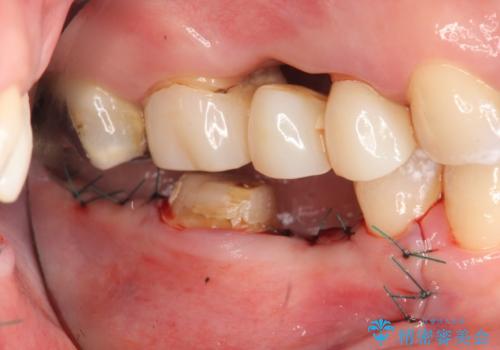

右下7は欠損しており、右下5は保存不可能だったため、インプラントによる欠損補綴を行いました。

インプラント埋入時には骨が不十分な部位に骨増生を行っております。

- オールセラミッククラウン…¥100,000×3、仮歯…¥10,000×3、インプラント(ストローマン)…¥200,000×2、カスタムアバット…¥100,000×2、骨増生…¥50,000費用は治療当時の料金となります